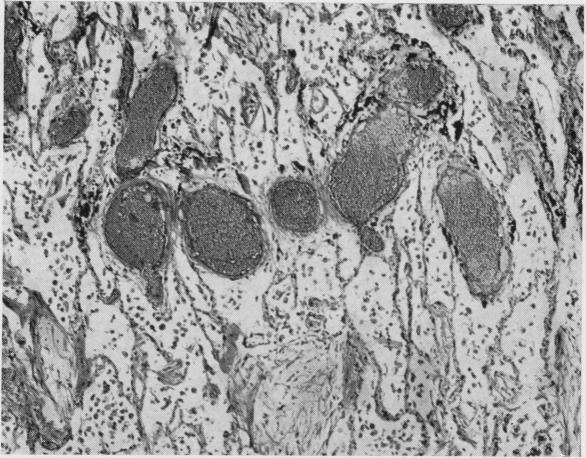

The morbid anatomical factors in the production of right heart hypertrophy and failure in emphysema have been reviewed with reference to 44 cases studied by standard histological methods and by post-mortem pulmonary arteriography. The most important factors in raising the pulmonary vascular resistance in these cases are considered to be vascular deformity and pressure by the emphysematous spaces on the adjacent branches of the pulmonary artery. Precapillary bronchopulmonary arterial anastomoses may be of importance in those cases where areas of localized bronchiectasis are present. Intimal fibrosis of the pulmonary arterioles, destruction of the pulmonary vascular bed, and thromboembolic phenomena were thought to be of only minor importance in the production of cor pulmonale in emphysema.

通过标准组织学方法和尸检肺血管造影术对44例病例进行研究,回顾了肺气肿导致右心肥大和衰竭的病态解剖学因素。这些病例中导致肺血管阻力升高的最重要因素被认为是血管畸形以及气肿腔对肺动脉相邻分支的压迫。在存在局限性支气管扩张区域的病例中,毛细血管前支气管肺动脉吻合术可能具有重要意义。肺小动脉内膜纤维化、肺血管床破坏和血栓栓塞现象在肺气肿所致肺心病的发生中被认为仅起次要作用。